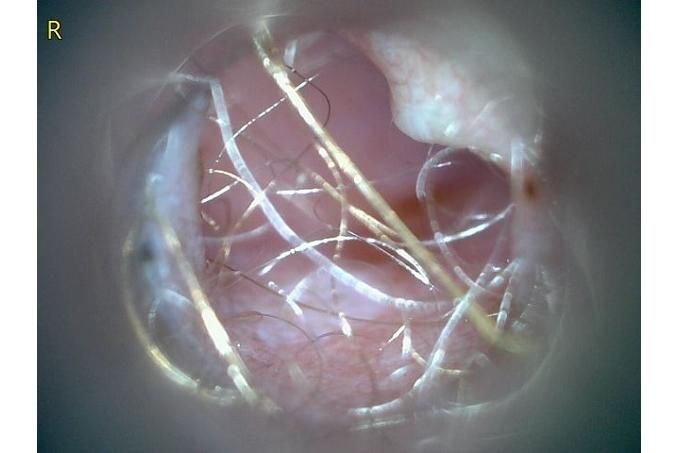

사진만 보고 확진할 수는 없지만 지금 올려주신 귀는 적어도 오른쪽은 정상으로 보이기 어렵습니다 왼쪽은 비교적 연분홍에 가까워 보이지만 오른쪽은 털과 분비물이 많이 차 있고 피부가 자극받은 듯한 모습이라 외이염 가능성을 먼저 생각하게 됩니다 그리고 질문자님이 적어주신 머리 털기 하루 여러 번 귀 만질 때 통증 솜만 닿아도 예민함 귀 긁기 같은 증상은 외이염에서 흔한 신호입니다